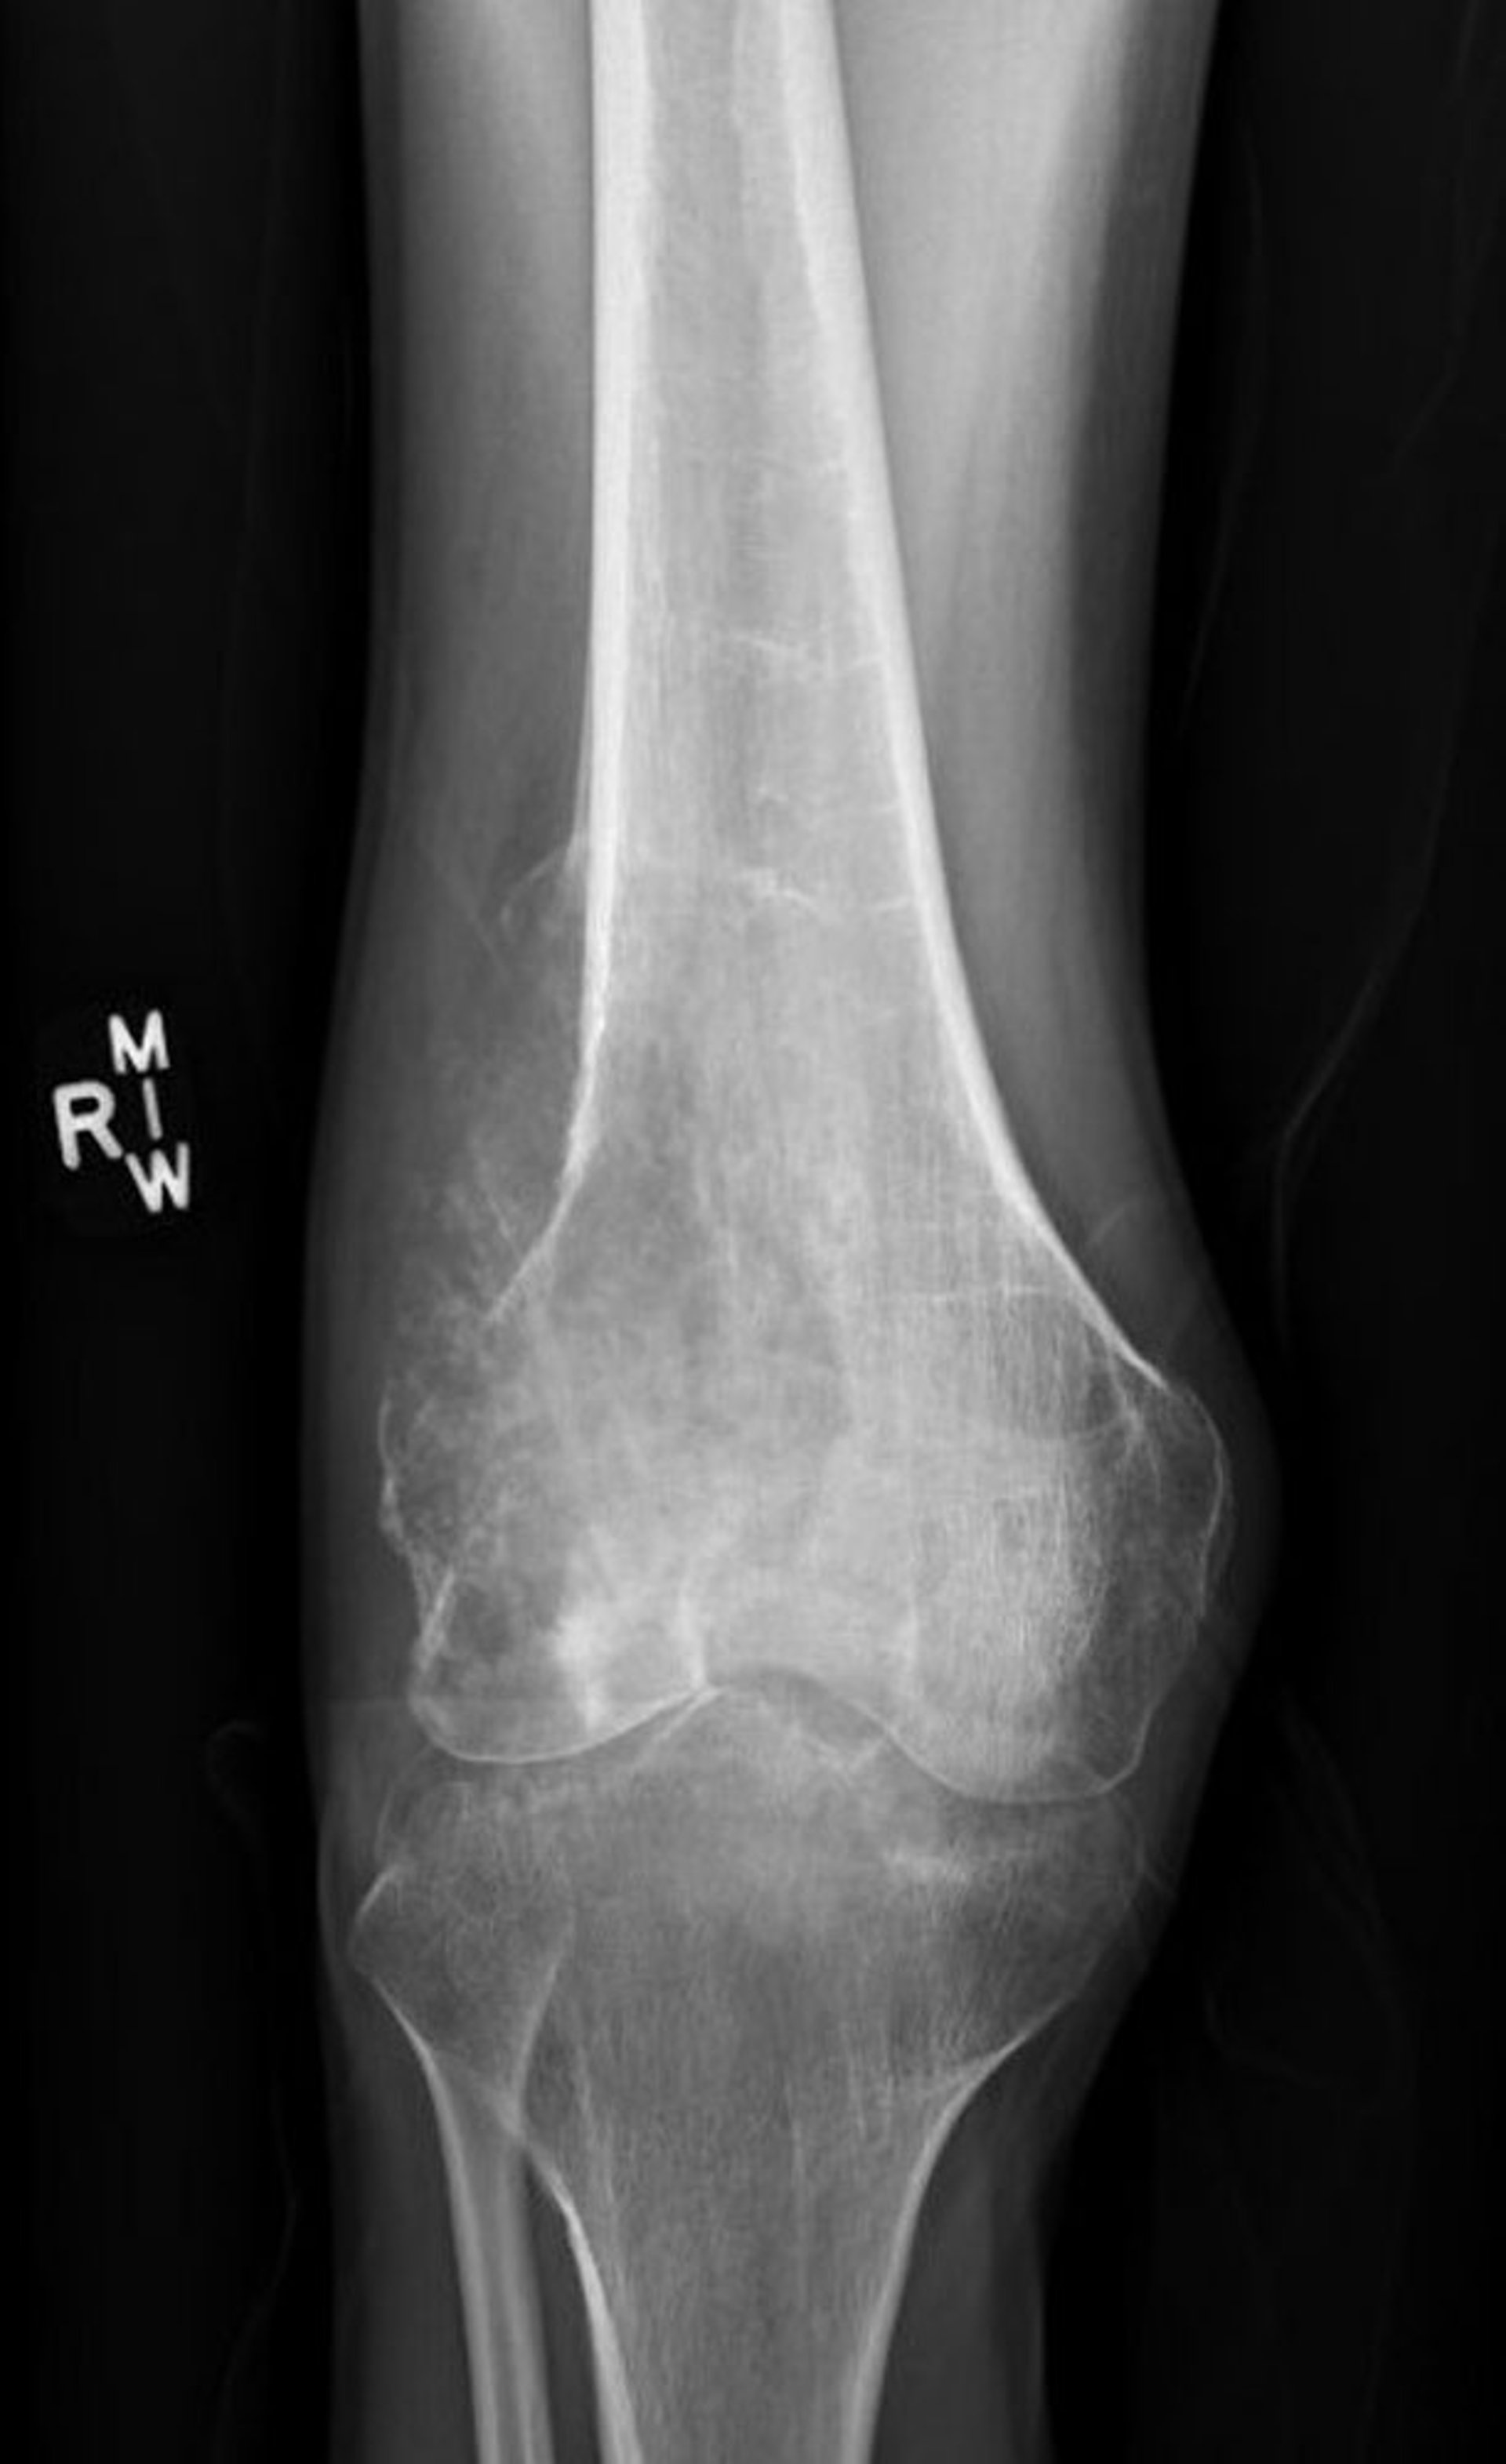

Остеосаркома

This radiograph of the knee shows a destructive osteosarcoma in the femur above the knee with a lytic destructive appearance and a classic Codman's triangle showing pathologic periosteal elevation.

Image courtesy of Lukas Nystrom, MD.